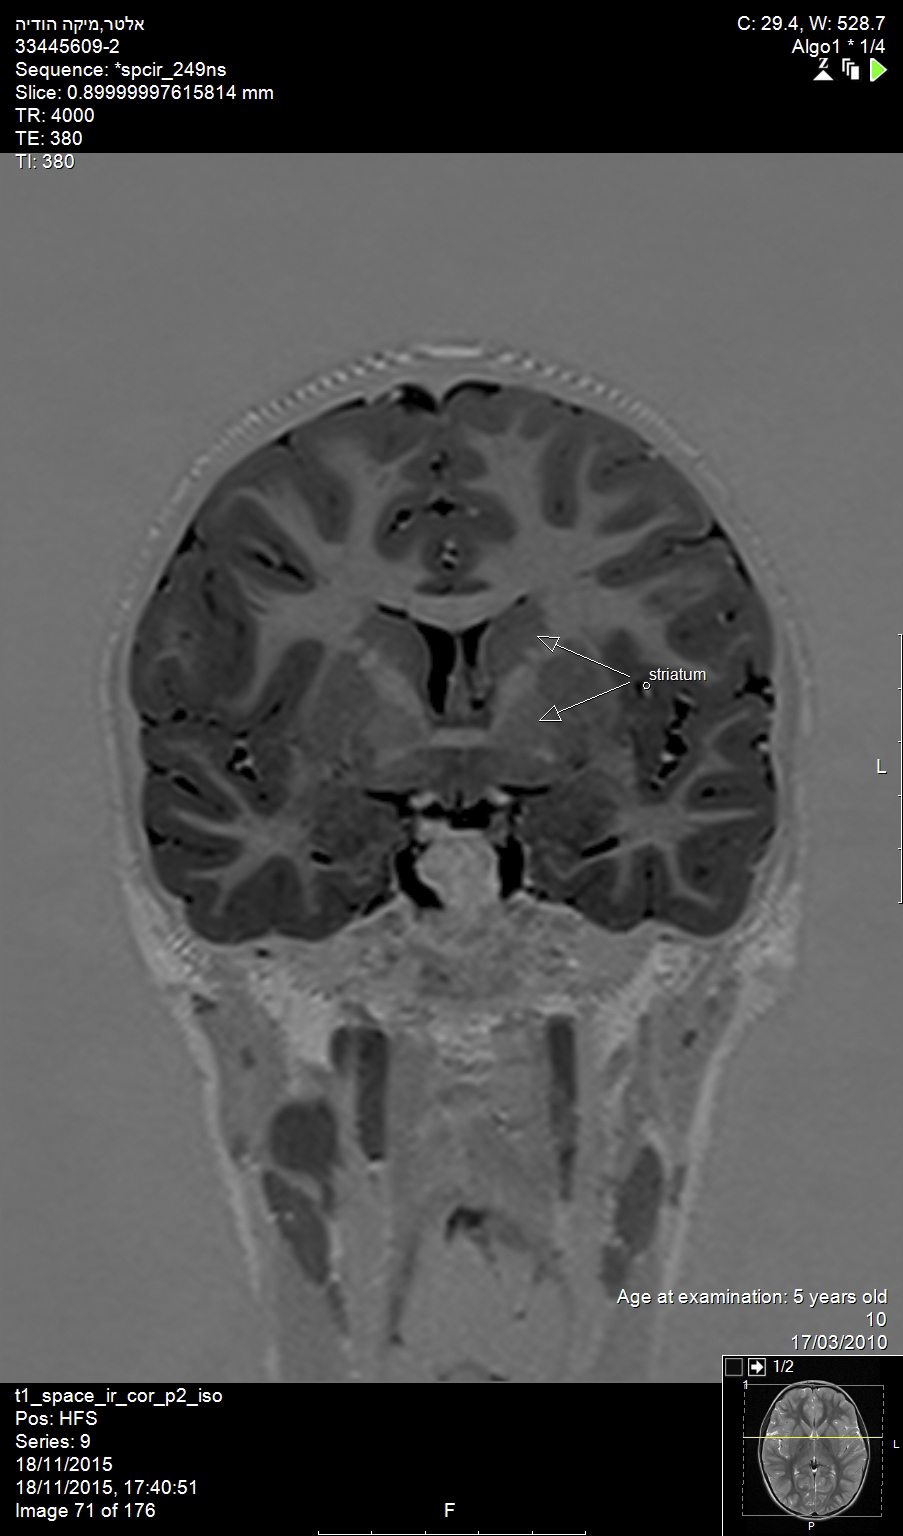

In the brain, Alzheimer’s disease and Huntington’s disease result in widespread loss of neurons (Figure 1), while Parkinson’s disease involves the specific and localized loss of dopaminergic neurons in the substantia nigra. In the brainstem and spinal cord, amyotropic lateral sclerosis and spinal muscular atrophy involve the degeneration and loss of motor neurons. While all of these conditions exhibit unique neuronal pathologies, the exact mechanisms for neuronal loss are complex, making the identification of efficacious treatments elusive.1

Fig 1. Alzheimer’s disease and Huntington’s disease result in widespread loss of neurons, as shown in this magnetic resonance image (MRI) of the brain of an elderly patient (top arrow: head of caudate nucleus; bottom arrow: putamen).

Figure 1